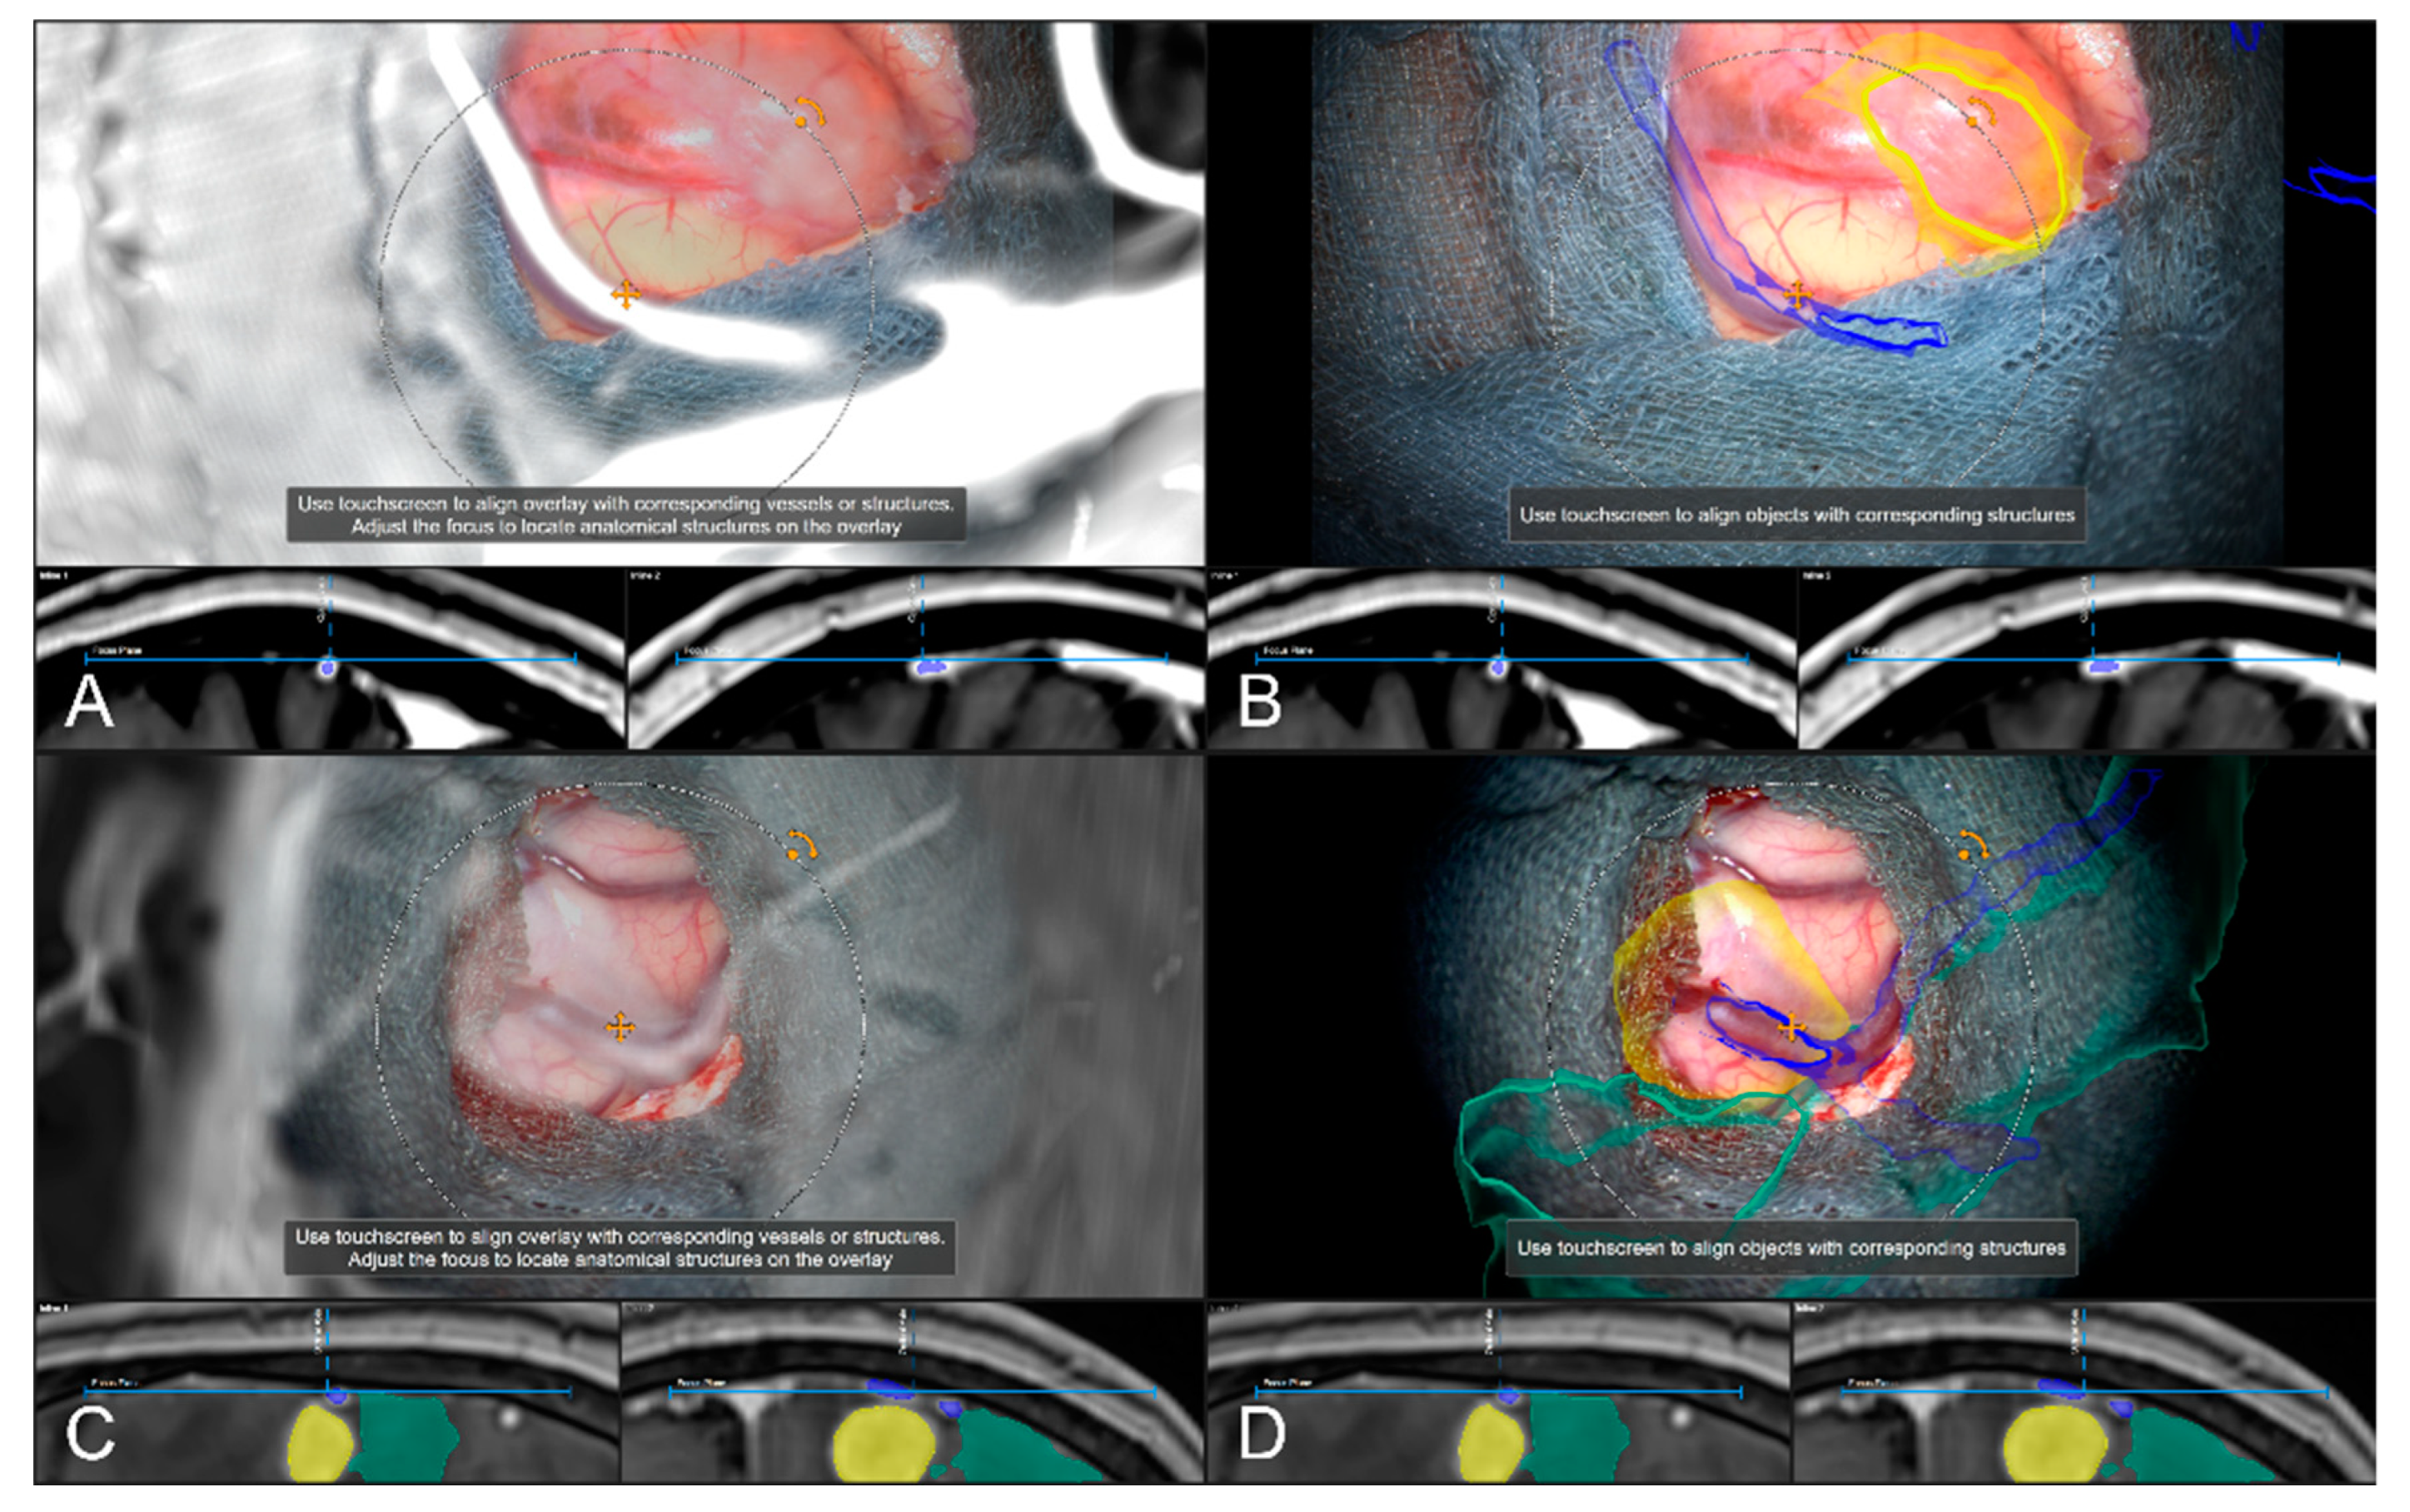

Figure 7. Navigation inaccuracy visualized in the recent focus plane utilizing a MIP of a preoperative T1-CE image showing the translational mismatch of MIP and patient anatomy (A,B) and the match of MIP and patients anatomy in the recent focus plane after manual correction (translation) of the visual misalignment (C,D). (In parallel view of MIP projection and patient anatomy (upper part) and inline views with the recent focus plane (blue line) and the optical axis (dashed blue line) in the bottom part).

Sensors 22 09591 g007

In 242 cases (82.59%), a vascular representation gained by available preoperative CTA, T1-CE, or ToF angiography data was used to evaluate navigation accuracy after dural incision, whereas in the remaining 18 cases (6.14%), no sufficient representation of cortical vascular structures could be obtained due to a lack of sufficient 3D data or poor contrast enhancement. In 43 out of those 242 cases (17.77%), a need to further realign the image data within the recent focus plane (see Figure 7) was seen, whereas in 181 cases (74.79%), navigation accuracy was determined to be sufficient (see Figure 8), partially due to prior evaluation utilizing bony landmarks. In all 43 cases, showing an inaccurate match of image and patient data, these local inaccuracies were successfully compensated for by rigid 2D transformation of the image data by translation on average of 3.00 ± 1.93 mm and a rotation on average of 0.38° ± 1.06°.

Navigation accuracy can also be evaluated using cortical vessels. After durotomy, the apparent cortical vessel structures can be used to investigate the accuracy, either verifying accuracy or trying to compensate for inaccuracies. A MIP representation is thereby created by image data ideally clearly picturing vessels, such as CT angiography data (CTA), T1 contrast-enhanced MRI data (T1-CE), or MR time-of-flight angiography data (ToF). Focusing on prominent cortical vessels, especially close to branching, within the surgical site the corresponding MIP representation of vessel structures is visualized, and navigational accuracy can be evaluated. If a mismatch is seen within the recent focus plane, those inaccuracies can be compensated again by a rigid transformation of the image data. In case a proper vessel segmentation is available besides the MIP representation also the object representation can be used. Especially in cases where no proper data for a MIP-based vessel representation is available a manual segmentation of cortical vascular structures within, e.g., T2 weighted MRI data can be utilized. If corrected, the new registration that is applied for further navigation needs to be verified as described above.